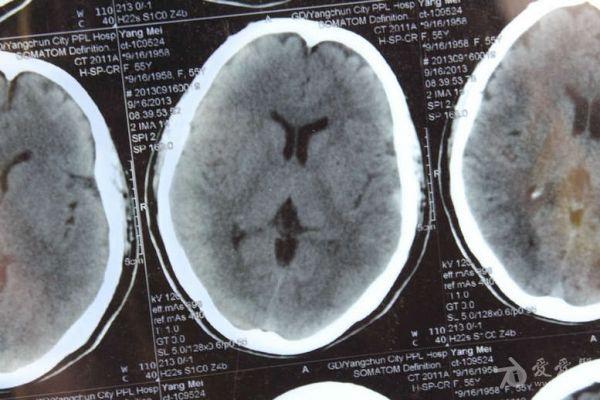

脑部占位病变CT,MRI图片,请帮忙诊断

最近感图样,无其它脑病病史

考虑脑膜瘤!!

磁共振没有平扫,增强矢状位没找到病灶。像脑膜瘤。

图片不是很清楚,应该是脑膜瘤!